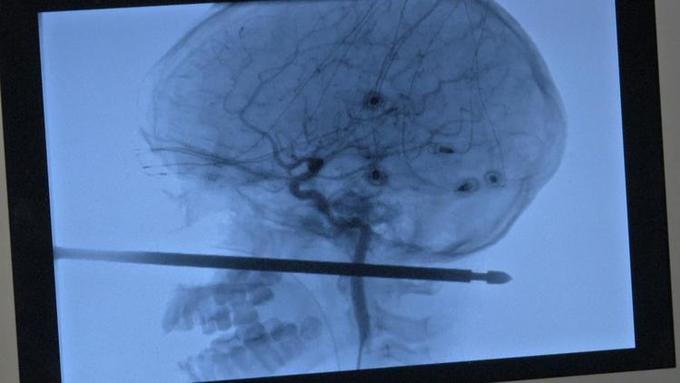

Xavier Cunningham, um menino de 10 anos, sobreviveu milagrosamente após ter a cabeça perfurada por um espeto de churrasco, no quintal da casa onde mora com a família, no estado do Missouri, nos Estado Unidos.

A criança brincava em uma casa na árvore, quando foi atacado por vespas e despencou com o rosto no objeto perfurante. Segundo os médicos, o espeto tinha 30 cm e destes, pelo menos 12 cm atravessaram a cabeça de Xavier, saindo na nuca.

A equipe que acompanhou e tratou o menino considerou o caso um verdadeiro milagre, já que o cérebro, os olhos , a medula e nenhum vaso sanguíneo foram atingidos na tragédia.